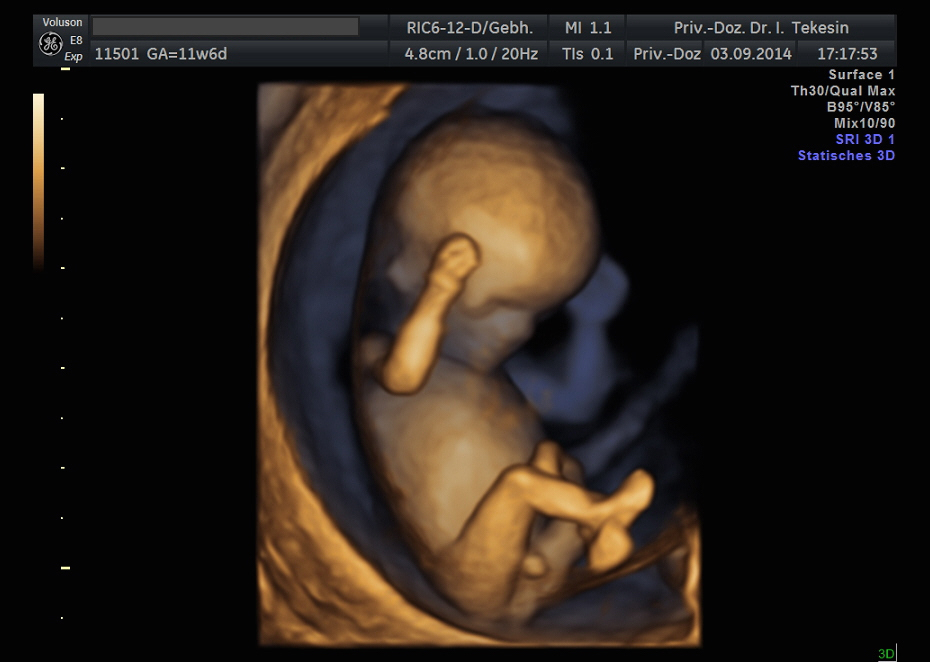

3D-/4D-Ultraschall (optional)

Immer mehr werdende Eltern interessieren sich für die faszinierenden Bilder, die dieses Verfahren liefert. Die plastische, dreidimensionale Darstellung der Oberfläche des Gesichts und anderer Körperregionen wird durch spezielle Bildrekonstruktion in schnellen Rechnern erreicht. Auch einzelne innere Organe oder „Gefäßbäume“ können von allen Seiten betrachtet werden. Viele dünne Schnittebenen (2D) werden zu einer gemeinsamen 3D-Sichtweise im Computer des Ultraschallgerätes zusammengeführt. Unter einem 4D-Ultraschall versteht man darüber hinaus eine 3D-Ultraschalluntersuchung unter Echtzeitbedingungen. Anstatt nur statische Bilder anzuzeigen, erfasst ein 4D-Ultraschall die Bewegungen des Kindes, weshalb er auch als „Live-3D-Ultraschall“ bezeichnet wird.

Diese Vorgehensweise ermöglicht äußerst realistische Bilder, bei denen sogar Gestik und Mimik des Kindes in bewegten Sequenzen festgehalten werden können. Die Untersuchung kann wie auch der normale Ultraschall während des gesamten Schwangerschaftszeitraums durchgeführt werden. Möchte man das Ungeborene komplett sehen, wird die 12. bis 16. Schwangerschaftswoche empfohlen, die Zeit zwischen der 28. und 33. Schwangerschaftswoche eignet sich besonders zur präzisen Darstellung einzelner Körperteile

Wir sehen in diesem modernen Verfahren in erster Linie eine ergänzende Maßnahme bei speziellen Fragestellungen bezüglich Herz, Gehirn oder Skelett und vor allem bei Verdacht auf eine fetale Besonderheit.

Kind in der 12. Woche

Kind in der 13. Woche

Kind in der 12. Woche (3D-Darstellung)

Kind in der 13. Woche (3D-Darstellung)